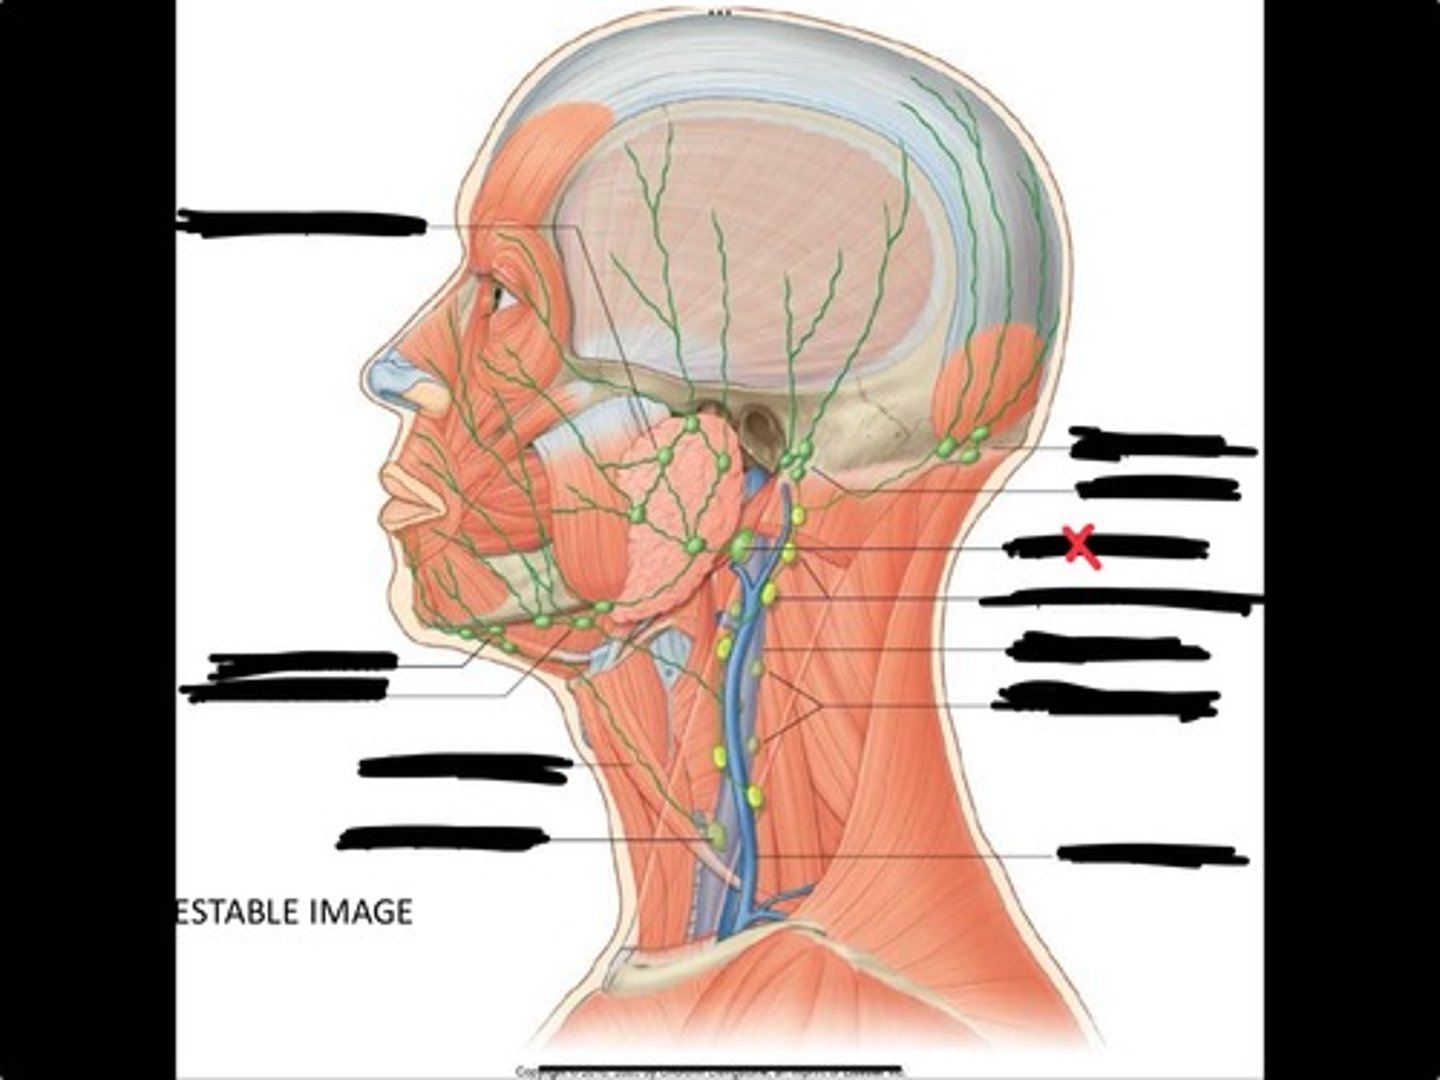

Jugulo-omohyoid node

Submandibular nodes

Submental nodes

Pre-articular/parotid nodes

Occipital nodes

Mastoid nodes

Jugulodigastric nodes

Superficial cervical nodes

Internal jugular vein

Deep cervical nodes

External jugular vein